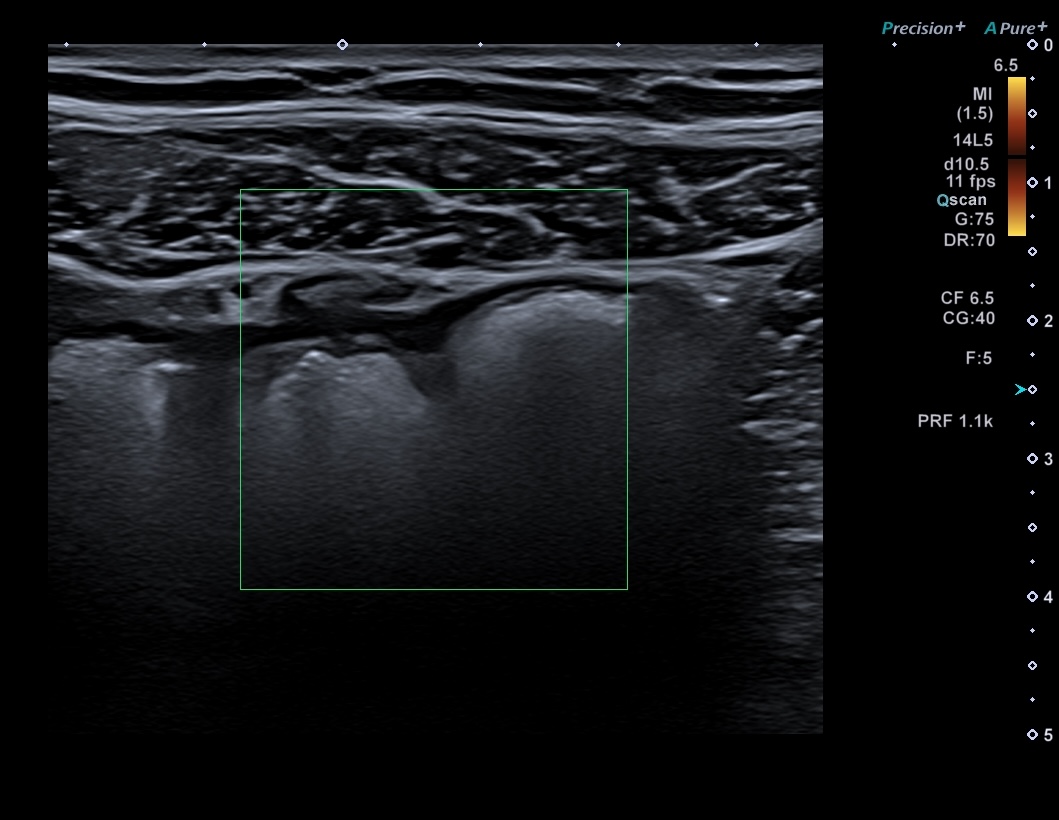

Patiente revue 4 ans plus tard sous vedolizumab Entiyo® en rémission clinique complète, biologie et calprotectine fécale normales, l’échographie (mauvaise échogénicité de la patiente) montre une paroi normalisée entre 1,8 et 2,8 mm d’épaisseur structure en couche conservée.

Le score de Milan MUC est à 3.92 confirmant la rémission échographique